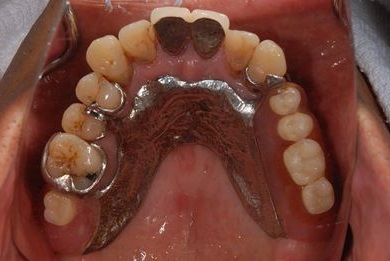

骨再生スピードインプラント治療+遊離歯肉移植

| 治療内容 | インプラント8本(サイナスリフト、抜歯即日スピードインプラント)、ハイブリッドセラミッククラウン9本、遊離歯肉移植 | ||||||||||||||||||||||||||||||||